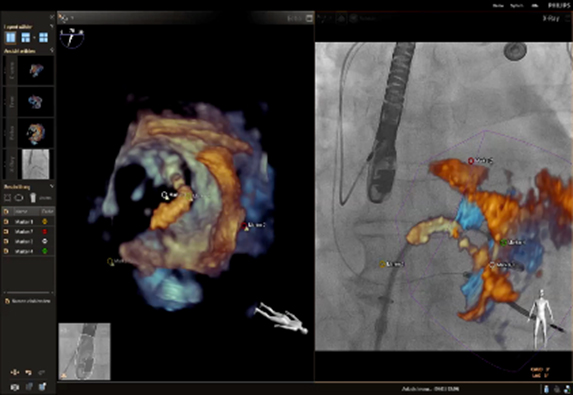

EchoNavigator

Azurion(아주리온)은 최신 인터벤션 소프트웨어가 탑재되어 있어 심혈관중재시술 시 더욱 용이하게 환자를 시술할 수 있도록 해준다. 최근 도입된 다이내믹 코로너리 로드맵(Dynamic Coronary Roadmap)과 스텐트부스트 라이브 (StentBoost Live)는 복잡하고 어려운 심장 혈관 및 심장 구조 질환의 치료에 성공적인 시술을 할 수 있도록 도와준다. 두 기술 모두 까다로운 심혈관중재시술 시 실시간 레퍼런스로 활용할 수 있어, 시술 시간의 단축, 방사선 피폭 및 조영제 사용량을 최소화할 수 있다.